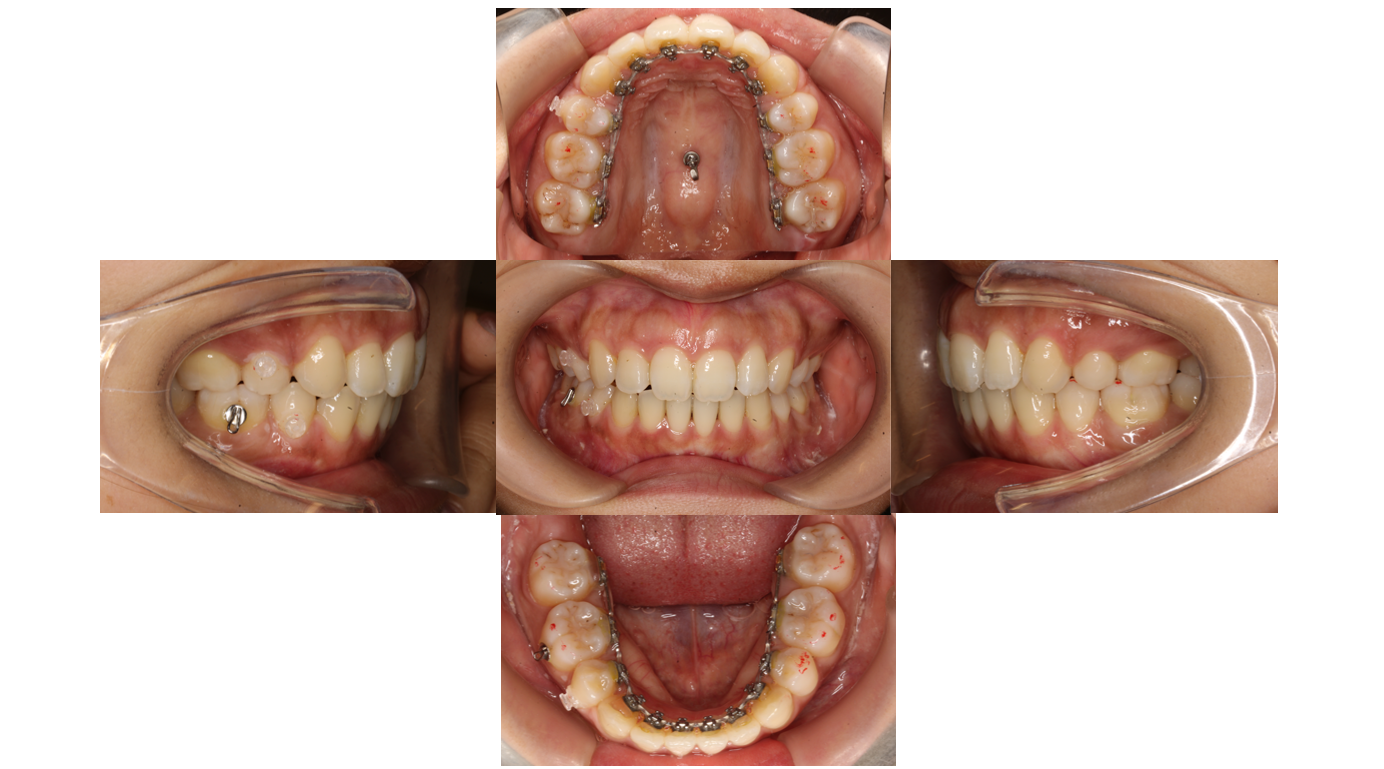

6か月経過

ワイヤーにフックを付けてネジからゴムを使用し前歯を後ろに下げます